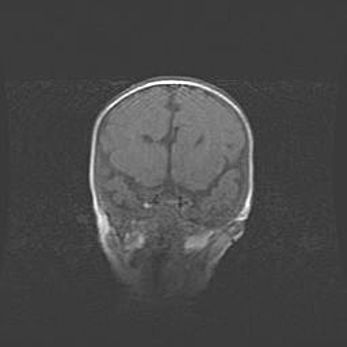

Наружная гидроцефалия с возможной атрофией височных областей.

Возраст: 28 дней

Вес: 3670 г

Пол: мужской

Окружность головы: 38 см

Срок гестации: 40 недель

Гидроцефалия головного мозга у новорожденных – это заболевание, которое характеризуется скоплением избыточного количества спинномозговой жидкости в желудочковой системе головного мозга в результате затруднения её перемещения от места выработки к месту поглощения в кровеносную систему или вследствие нарушения абсорбции. При открытой наружной форме гидроцефалии у новорожденных расширяются и переполняются субарахноидные пространства.

При нормотензивных  формах,  которые,  как  правило,  являются  следствием  перенесенных ишемических  повреждений  паренхимы  мозга,  возможно  сочетание микроцефалии  с нормотензивной гидроцефалией. В основе данных изменений лежит атрофия больших полушарий с преимущественной  локализацией  в  лобно-височных  областях.